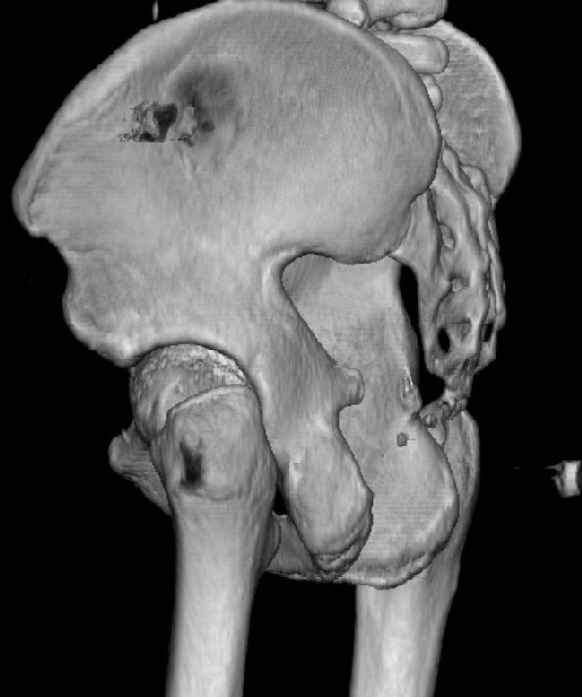

Some more images. Does it help to guess which part of the acetabulum is displaced?

Normal appearing SI joints and a healed posterior column limb... my bet's on caudal segment displacement.